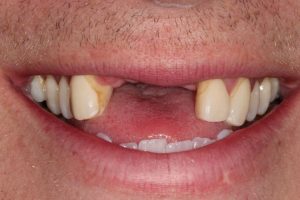

Broken Upper Front Tooth

The upper right central incisor tooth broke and was irreparable. Following removal of this tooth, and implant was placed on the same day as well as a temporary crown. This gave the patient a replacement tooth immediately and after 3 months of healing, a more definitive crown was made to match closely the adjacent tooth.